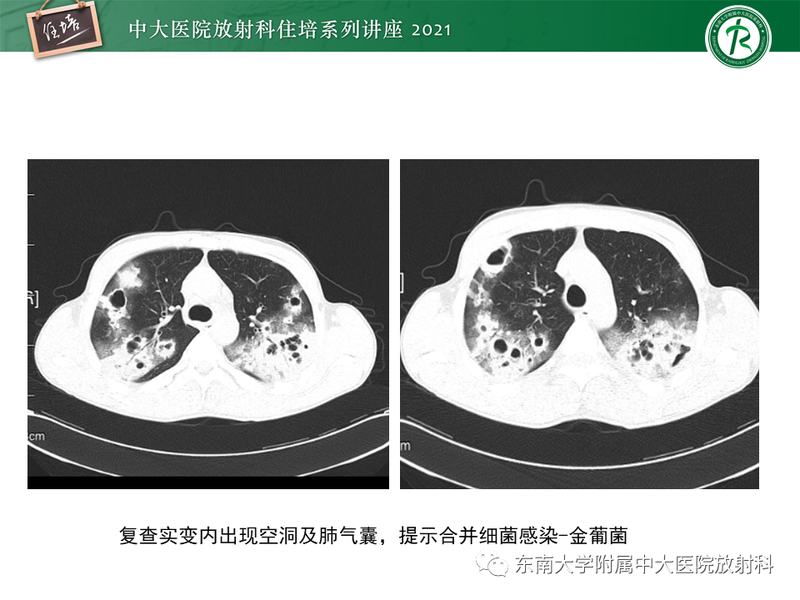

常见细菌性肺炎、病毒性肺炎影像诊断与鉴别